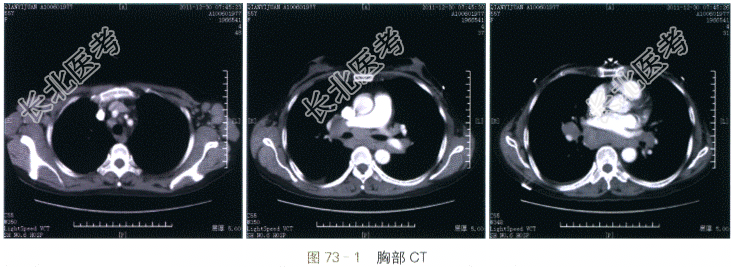

胸部CT增强扫描(见图73-1)提示双侧腋下、肺门及纵隔多发肿大淋巴结,密度均匀,中度强化,部分淋巴结融合成团。

读片分析:本例患者的病灶为多发,双侧腋下、肺门及纵隔均可见肿大成团的淋巴结。淋巴结内未见明显钙化,增强后表现为均匀强化的实质性病灶。肺内未见明显结节灶。鉴别诊断主要考虑淋巴瘤、淋巴结转移、结节病以及淋巴结结核。首先该病灶为均匀非环形强化,且肺内未见病变,故淋巴结结核的可能性小。其次双侧腋下亦可见肿大淋巴结,结节病的可能性也较小。该患者无明确原发肿瘤病史,因此最终诊断将淋巴瘤放在首位。手术病理证实该例患者为滤泡性淋巴瘤。